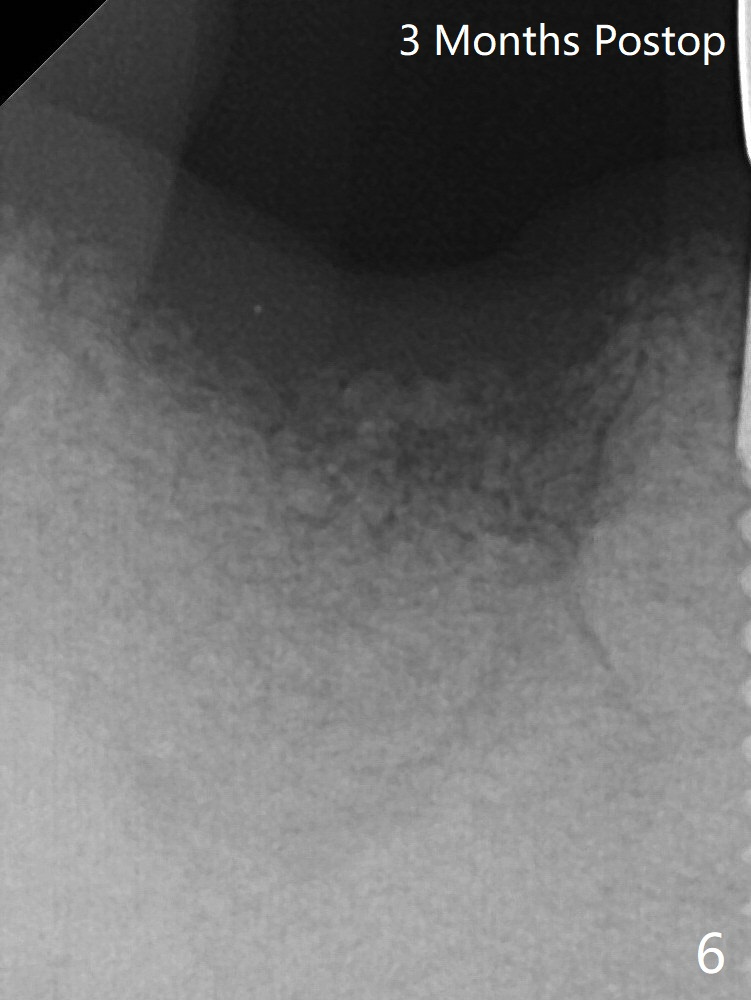

After discussion, the tooth is extracted with socket preservation (Vanilla graft mixed with Osteogen, covered with Osteogen plug and Collagen plug, Fig.3).  The bone volume reduces, especially height, 3 months postop (Fig.6).